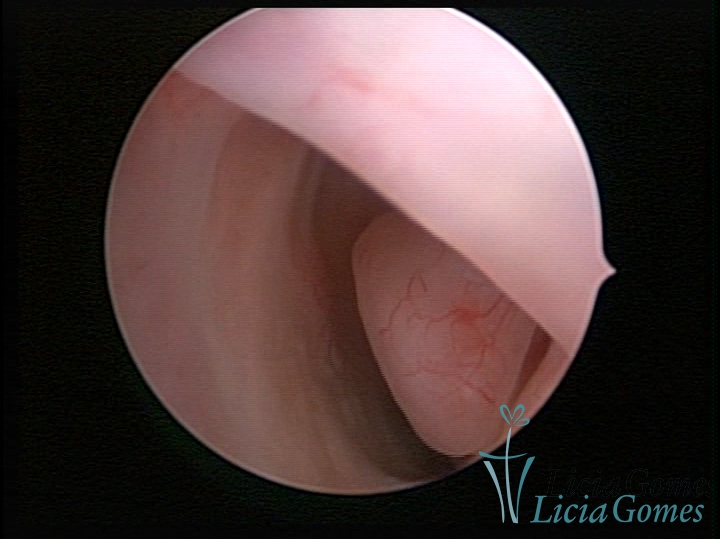

ENDOCERVICAL POLYPS

Benign tumors resulting from the reactive focal proliferation to inflammatory processes or hyperestrogenism situations, which may be sessile (with a large implantation) or stalked.